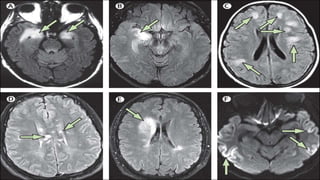

 MRI: better with contrast, < 50% positive. When positive > e.g. Medial

temporal hyperintensity.